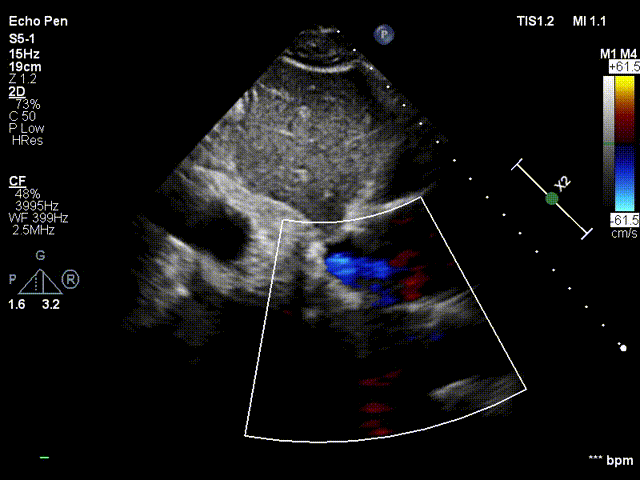

术后即刻分流器稳定,可见左向右分流束。

与基线访视水平相比,术后1个月随访时患者的活动耐量显著改善,患者NYHA II级降低至NYHA I级,堪萨斯心肌病问卷评分从57分升高至82分,NT-proBNP从基线时2461pg/ml降低至558pg/m,六分钟步行距离从448米升高至585米。从超声心动图指标观察到患者基线时左心室射血分数为24%,1个月随访时为44%。平均左室收缩末期内径为60 mm,1个月随访时为50mm。平均左室舒张末期内径为68mm,1个月随访时为63mm。肺动脉收缩压26mmHg,1个月随访时为23mmHg。超声可见心房左向右稳定的分流血流信号,缓解左房压。分流孔径最大直径和最小直径分别是4.2mm和3mm,分流孔径保持良好。结果可见SIRIUS AFR心房分流器系统植入后患者的前期左心血流动力学状态有所改善。

经胸超声可见分流器形态良好,无血栓

经胸超声可见左向右分流束